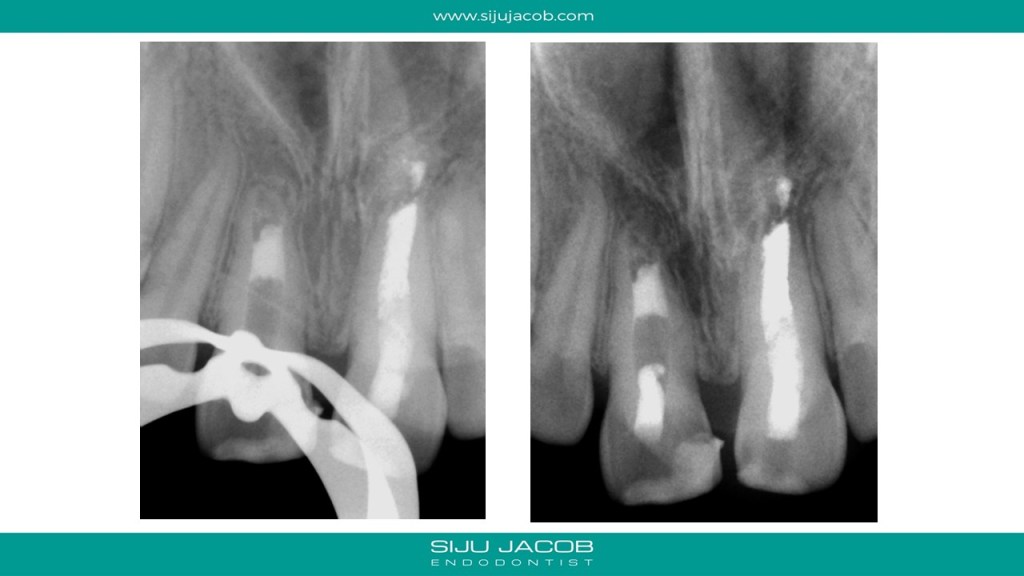

This was probably the largest lesion I ever treated. It had several interesting characteristics. It would be tough to explain with just pics. So, I made it into a short presentation